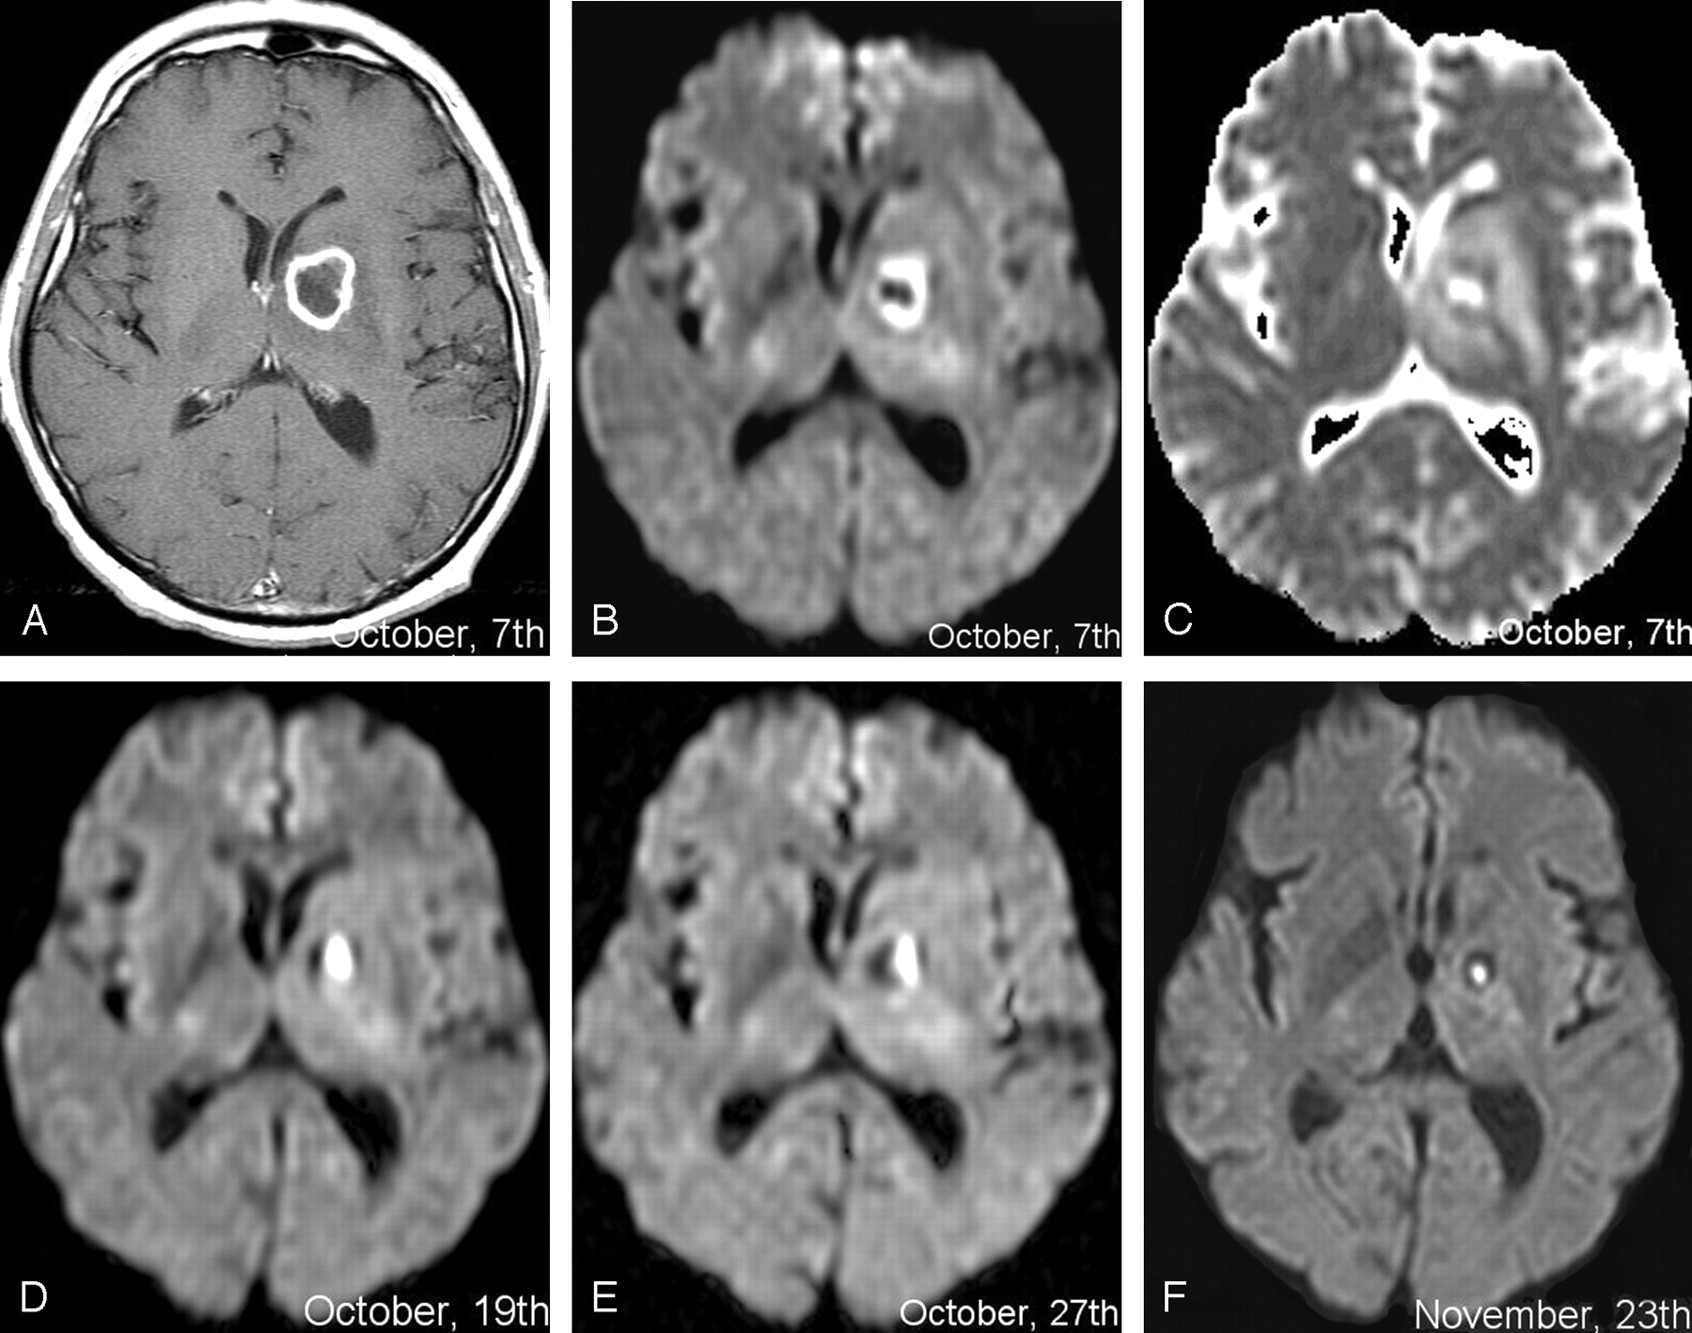

We recently observed a 61-year-old man with non-Hodgkin lymphoma who complained from tiredness, atypical sensory disturbances of the four extremities, and gait disturbances without fever. Initial MR examination demonstrated the presence of a left-sided deep nodular lesion. Intensely enhanced margins surrounded a central area of cystic necrosis (Fig 3A). DW trace images revealed a sharply delineated hypo-/hyperinterface with ringlike pattern (Fig 3B). The peripheral component was hyperintense, but had slightly elevated ADC values when compared with normal brain tissue (Fig 3C), just as the shrinking hyperintense core in the previous patient. The central component was hypointense with highly elevated ADC values, which has not been described yet in brain abscesses involving pyogens. Empirical antibiotic therapy was unsuccessful. Stereotactic biopsy evacuated purulent material containing neutrophilic pyocytes. The causative germ remained unidentified. Antibiotic treatment was continued after drainage, and serial follow-up MR examinations were performed (Fig 3D–F). The first follow-up examination performed 2 days after stereotactic procedure showed inverted hypo-/hyper-ring pattern with central hyperintensity and peripheral hypointensity (Fig 3D). Further examinations demonstrated the progressive shrinkage of hyperintense core and the persistence of hypointense margins (Fig 2E, -F).

Patient 2.

A–C, Initial MR examination at admission. A, Postcontrast T1-weighted image shows a left-sided ring-like lesion with central cystic necrosis and enhanced peripheral margins. B, DW trace image shows sharply delineated central hypointensity and peripheral hyperintensity of the lesion. The pattern is up to now undescribed in pyogenic abscesses. C, ADC-mapped image shows strongly increased ADC values within the center of the lesion (mean, 2320) and moderately increased ones within the peripheral ring (mean, 1210). Mean ADC value in normal contra lateral mirror area was 830.

D–F, Serial follow-up DW images after stereotactic drainage and during consolidation antibiotic treatment. D, Lesion pattern has inverted when compared with the pretherapeutic status (Fig 2B): central area has now become hyperintense and peripheral one has become hypointense. E and F, Shrinkage of the central hyperintense component over time is obvious.